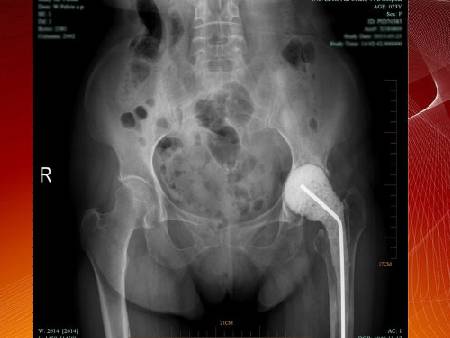

大家來找茬:請找出下圖中的兩條腿,有哪兩處不同?這是一張有問題的腿的片子,問題出在哪兒?這些問題說明身體什么問題?敬請收看4月3日衛(wèi)生部中日友好醫(yī)院脊柱外科主任李中實(shí)教授,為您講述《健全骨骼 強(qiáng)韌有方》。